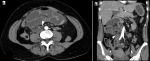

Diagnostic assessment: i) X-ray: plain abdominal radiography demonstrated small bowel air-fluid levels predominantly in the right mesogastric region, without pneumoperitoneum (Figure 1); ii) computed tomography (CT) scan: contrast-enhanced CT confirmed small bowel obstruction due to an internal hernia, with features suggestive of a right paraduodenal hernia (Figure 2-5); iii) laboratory tests: laboratory tests showed leukocytosis with a white blood cell (WBC) count of 12,400/mm3, while liver and kidney function tests, pancreatic enzymes, ionogram, C-reactive protein (CRP), and coagulation profile were all normal.

Figure 5: A,B) show internal hernia containing jejunal bowel loops just beyond the duodenojejunal junction with transition point noted at the white arrow head to the right of the spine